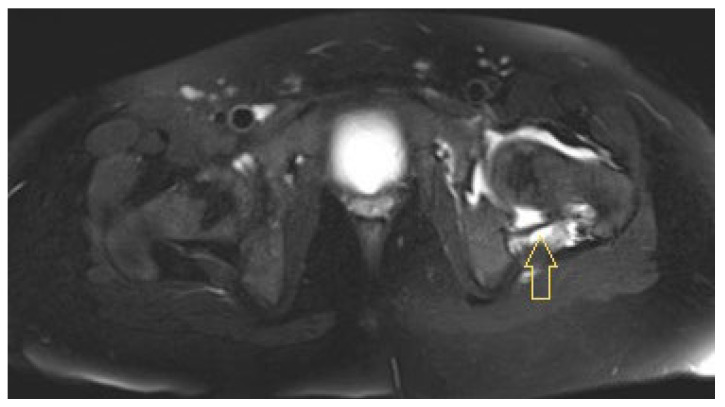

Background: In paediatric osteoarticular infections, microorganism detection is unsuccessful in up to 55% of cases, which is not satisfactory for targeted antibiotic therapy. In particular, anaerobic fusobacteria may be underdiagnosed owing to a lack of knowledge about their properties. Methods: Based on three of our own cases and a systematic literature review regarding paediatric osteoarticular fusobacterial infections, we extracted characteristic variables and synthesised them in terms of frequencies and mean comparisons. We followed the CARE and PRISMA guidelines. Results: In our three patients with hip area infections (aged 11, 12, and 16 years; two males and one female; two with Fusobacterium nucleatum [FNU] and one with Fusobacterium necrophorum [FNE]), we only detected FNU with PCR. The patient with an FNE infection showed a septic and protracted course with six surgical interventions and secondary coxarthrosis during the follow-up. The FNU infections were milder and healed without sequelae. In the literature, there are no articles with more than 3 cases; overall, we identified 38 case reports and 3 case series with a total of 45 patients. Across all synthesised cases (73% boys), the age was 9.2 ± 4.1 years. Most patients (42%) were affected by hip joint arthritis, with or without accompanying acetabular or femoral osteomyelitis, followed by knee joint arthritis, with or without osteomyelitis, in 24% of patients. In 49% of cases, there was an ear, nose, and throat focus. Depending on the affected structure, arthrotomy (33%), arthroscopy (11%), bone (24%), and soft tissue (9%) debridement were performed, with 34% of the procedures having to be performed several times. Penicillins, metronidazole, and clindamycin were the most used antibiotics. In 32 cases (71%), the authors reported healing without sequelae. Conclusions: When samples are collected in the operating theatre for paediatric osteoarticular infections, orthopaedic surgeons should also ensure correct anaerobic sampling and consider the possibility of performing PCR. A typical child with an osteoarticular fusobacterial infection is a boy of approximately 10 years of age with an infection in the hip area and a previous infection in the ENT area.